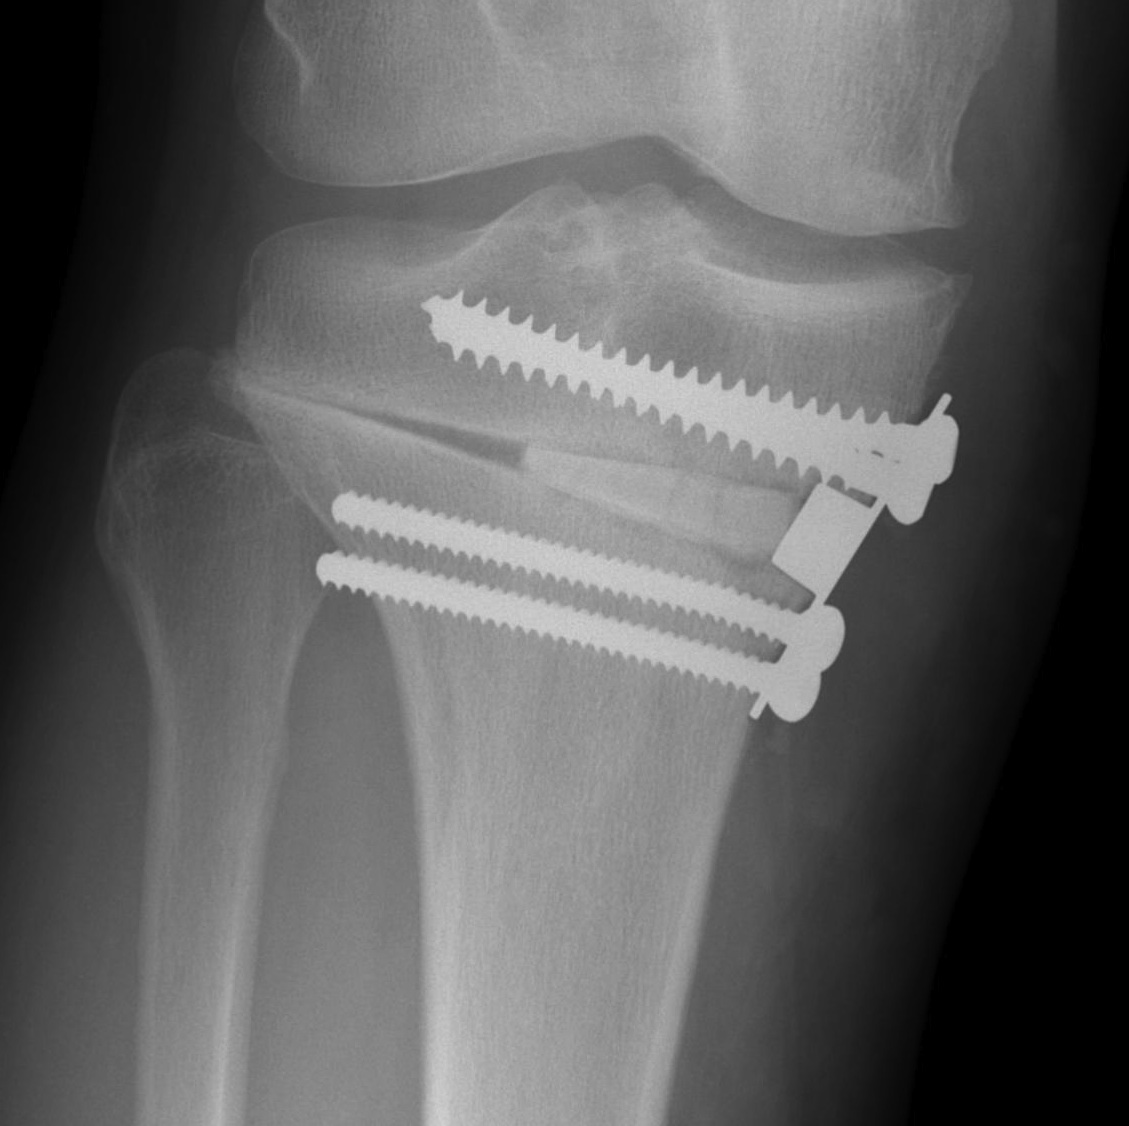

Management

Type I: limit weight bearing 6 weeks

Type II / displacement: lateral plate

Instability

- place a Richards staple / plate over lateral fracture site